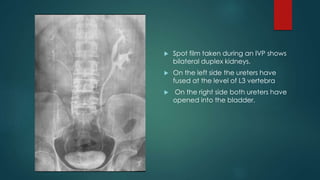

 Spot film taken during an IVP shows

bilateral duplex kidneys.

 On the left side the ureters have

fused at the level of L3 vertebra

 On the right side both ureters have

opened into the bladder.